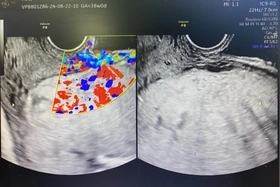

baophutho.vn Các bác sĩ tại Trung tâm Y tế huyện Đoan Hùng vừa phẫu thuật thành công cho người bệnh N.T.H, 41 tuổi, xã Phú Lâm, huyện Đoan Hùng chửa ngoài...

baophutho.vn Vừa qua, các bác sĩ Khoa Phụ sản và Chăm sóc sức khỏe sinh sản (CSSKSS) – Trung tâm Y tế huyện Cẩm Khê đã phẫu thuật lấy thai thành công cho...

baophutho.vn Các bác sĩ Khoa Sản 1, Bệnh viện Sản Nhi tỉnh Phú Thọ vừa phẫu thuật lấy thai thành công cho sản phụ N.T.H, 30 tuổi, trú tại xã Bằng Doãn,...

baophutho.vn Khoa Phụ sản, Trung tâm Y tế huyện Đoan Hùng vừa cấp cứu thành công trường hợp sản phụ H.T.T., 39 tuổi, huyện Tân Yên, tỉnh Bắc Giang nhập viện...

baophutho.vn Ngày 17/4, đại diện Bệnh viện đa khoa thị xã Phú Thọ cho biết các bác sĩ đã phẫu thuật mổ thành công một sản phụ mang thai lần đầu, có thai nhi...